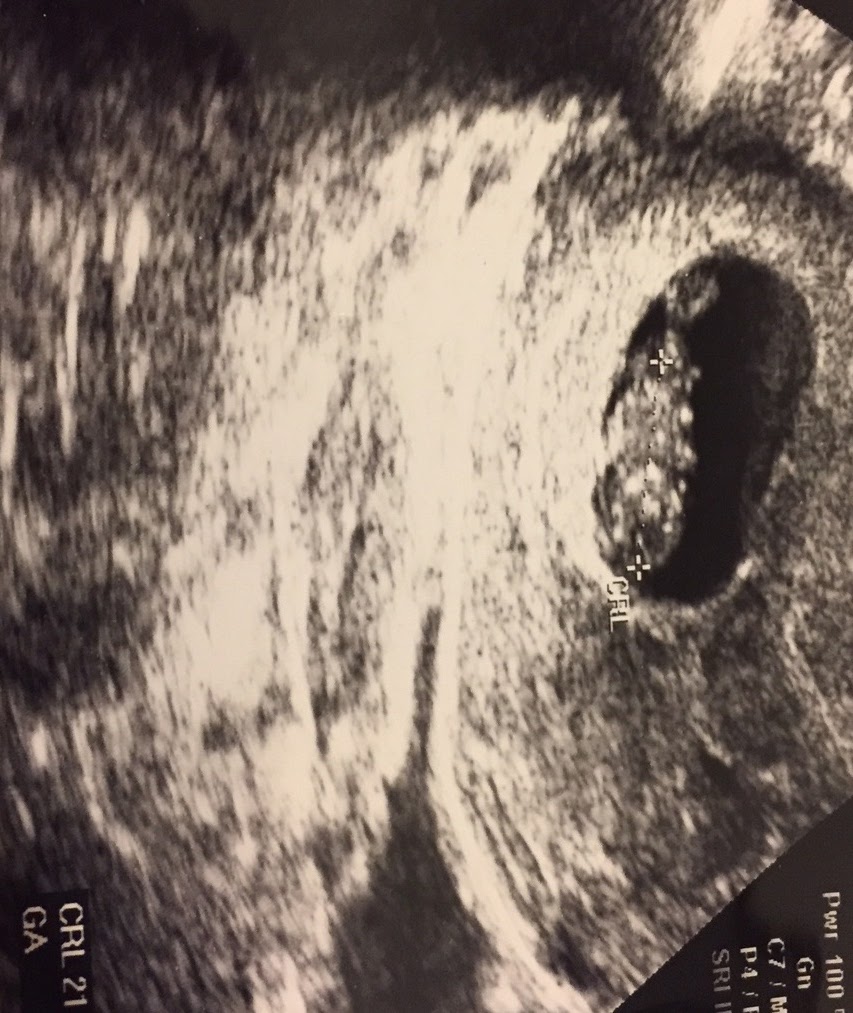

9 Haftalık Gebelik Ultrason Görüntüleri, Anne, Bebek

9 Haftalık Gebelik (Hamilelik) Ultrason Görüntüleri